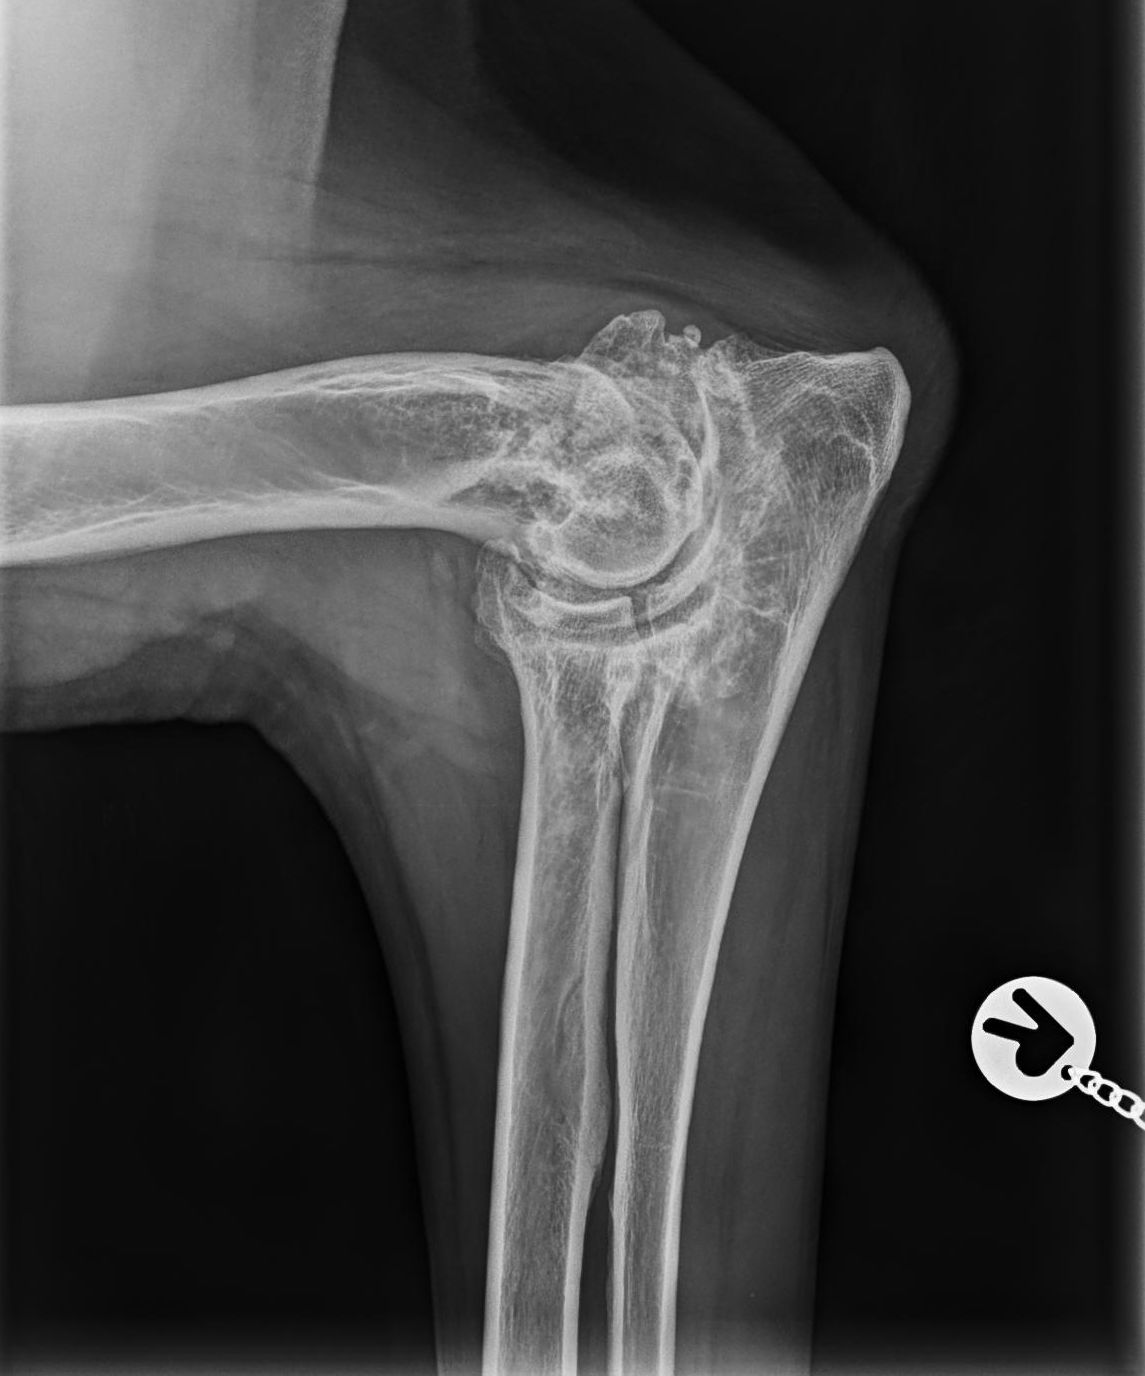

OCD – Röntgenuntersuchung des Schultergelenks

OCD oder auch Osteochondrosis dissecans entsteht durch eine Wachstumsstörung des Schultergelenks. Wiederum kommt die Erkrankung bei großen Rassen vor und entwickelt sich in der Regel beim Junghund zwischen vier und zwölf Monaten.

Bei der OCD löst sich – aufgrund einer Mangeldurchblutung – ein kleines Stück des Gelenksknorpels ab, wodurch eine Entzündung entsteht, die zu einer schmerzhaften Lahmheit führt. Wird das Knorpelstück entfernt, kann es zur völligen Ausheilung mit einer guten Prognose kommen.

Neben dem Schultergelenk können auch das Ellbogengelenk, sowie Knie und Sprunggelenk von einer OCD betroffen sein.

OCD Frei

OCD